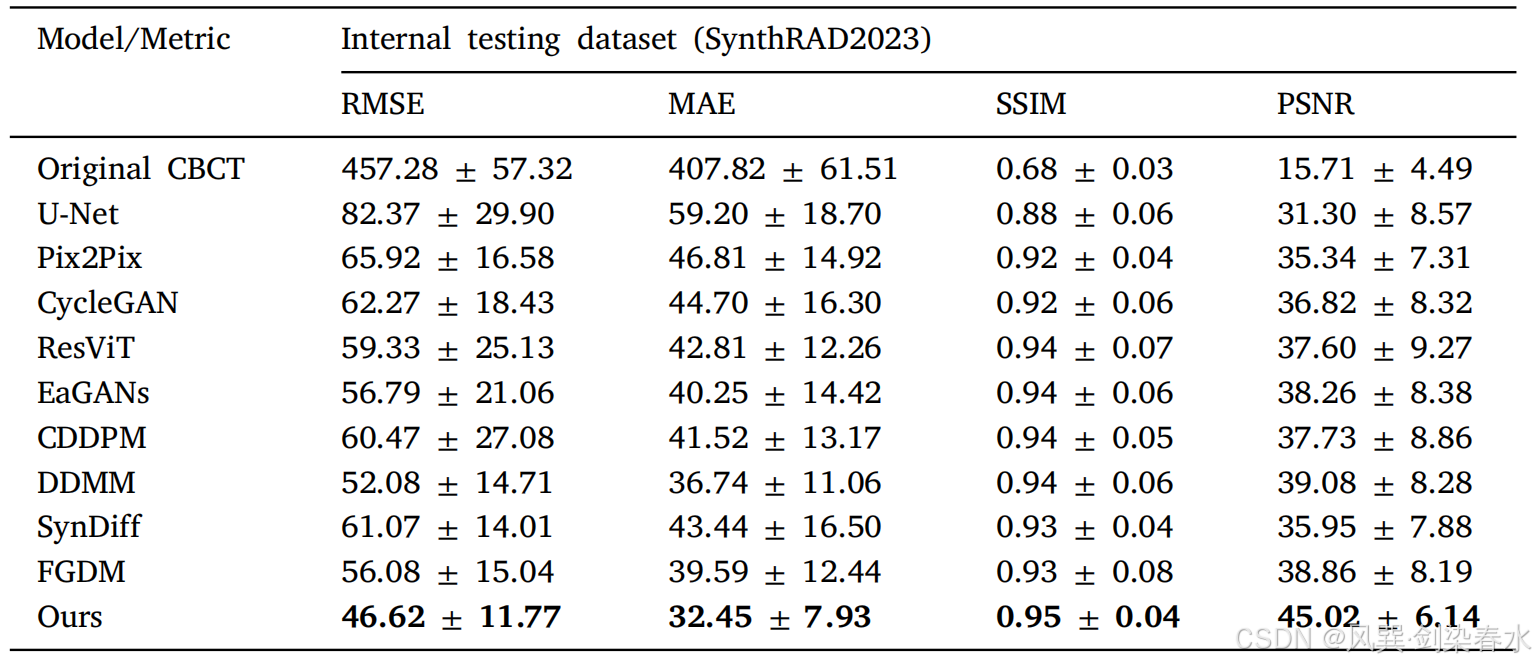

Table 1 | 内部骨盆测试数据集的实验结果:

Table 3 | 头部测试数据集的实验结果: